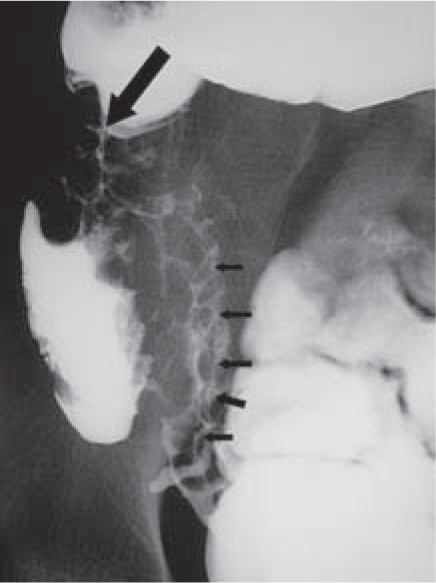

Crohns Disease X-Ray This lower abdominal X-ray shows narrowing stenosis of the end of the small intestine ileumwith loss of mucosal pattern and bowel wall thickening. However CD may also have extraintestinal manifestations which occur in at least 25 of CD patients. Crohns disease CD is a granulomatous systemic disorder of unknown etiology commonly involving the gastrointestinal tract.

This lower abdominal x-ray shows narrowing stenosis of the end of the small intestine ileum caused by Crohn disease. One of the most common is an abdominal X-ray. The role of cross-sectional imaging in the diagnosis of Crohn disease has expanded with recent technologic advances in computed tomography CT and magnetic resonance MR imaging that allow rapid acquisition of high-resolution images of the intestines.

When it passed into the small intestines this x-ray was taken lower GI series.

A solution containing a dye barium was swallowed by the patient. When it passed into the small intestines this x-ray was taken lower GI series. Imaging can help direct therapy and can predict important patient outcomes. Crohns disease typically affects the small intestine. Crohns disease typically affects the small intestine. Imaging the gut provides information on Crohns disease activity identifies complications and provides insight into patient symptoms. Crohn disease typically affects the small intestine whereas ulcerative colitis typically affects the large intestine.